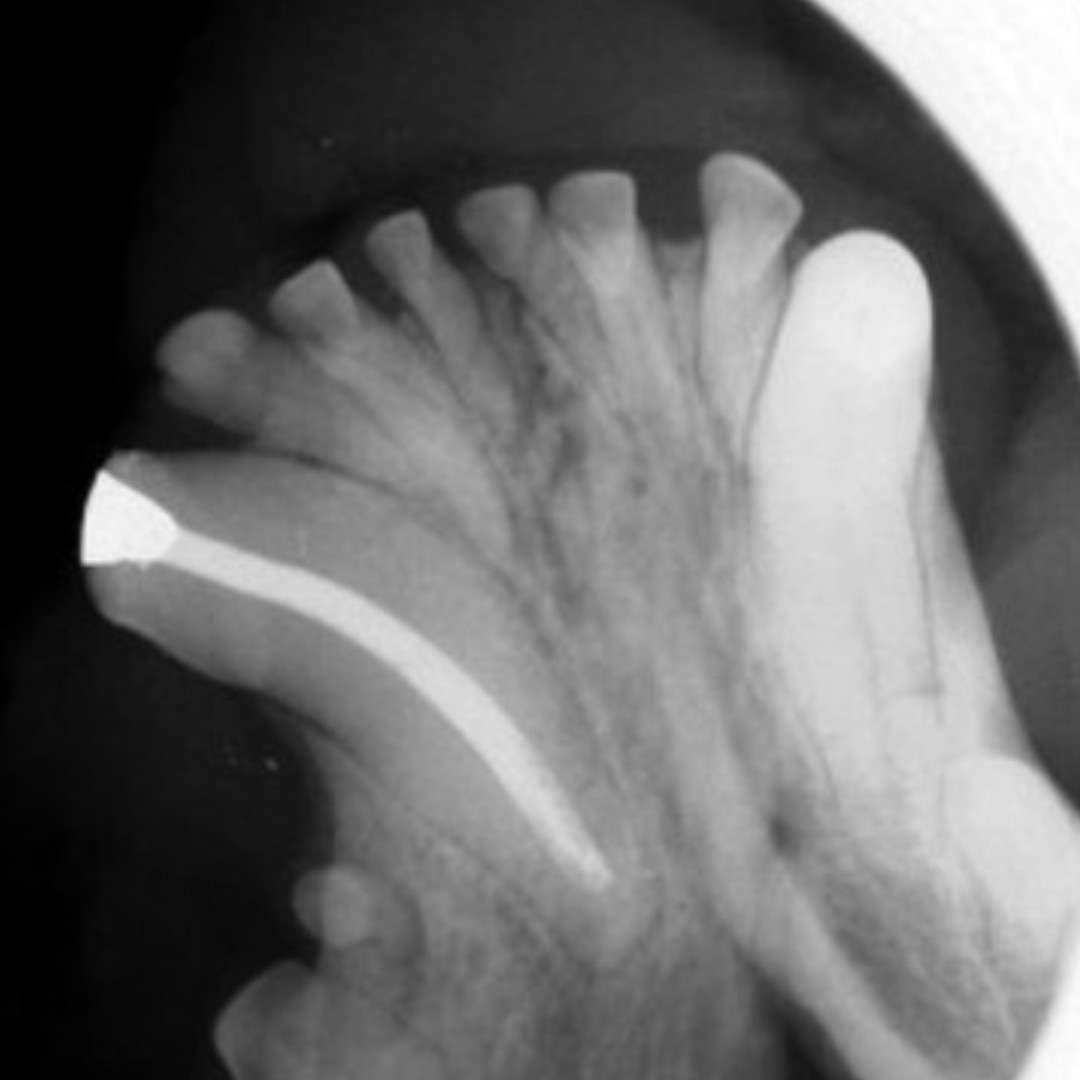

Hallmark Dental Laboratory Ltd. is a full-service dental lab that provides services to dentists across Canada. We specialize from dentures to crown & digital